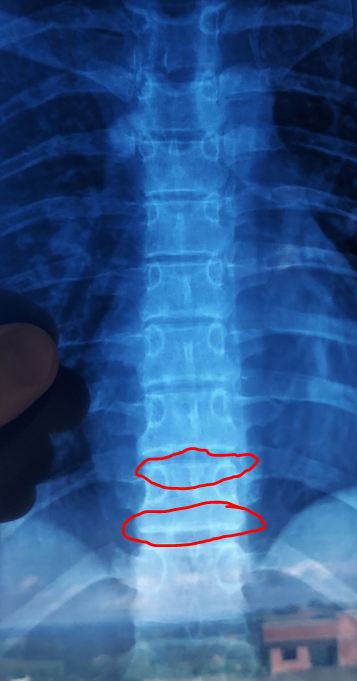

spine xray from one month ago

Diagnosed with a pituitary gland tumor (this gland secretes GH) at the age of around 17. He grew ten inches that following year. Most of the growth is in his spine as you can see since his spine is longer than his legs.